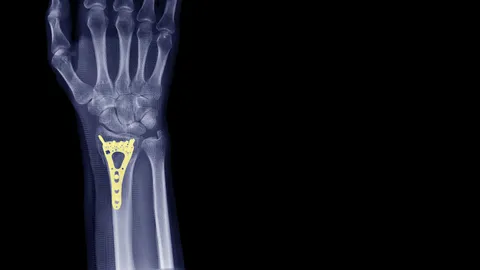

พัฒนาแผ่นดามกระดูก เพิ่มแกร่ง “กันแตกหัก”